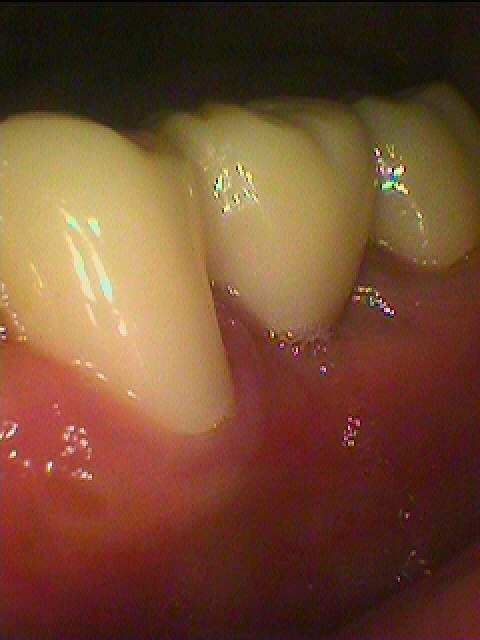

ジルコニアブリッジが入りました

綺麗に仕上がりました